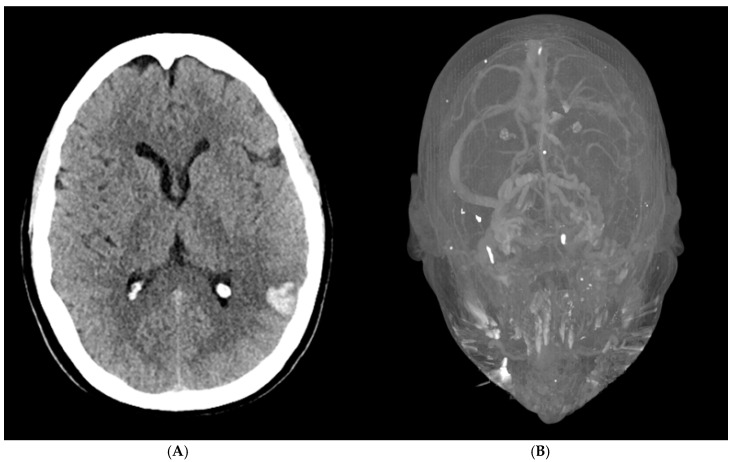

Case presentation: We report a case of S-HIT associated with pulmonary artery embolism, left internal jugular vein, and cerebral vein sinus thrombosis complicated with ipsilateral acute intracerebral hemorrhage.